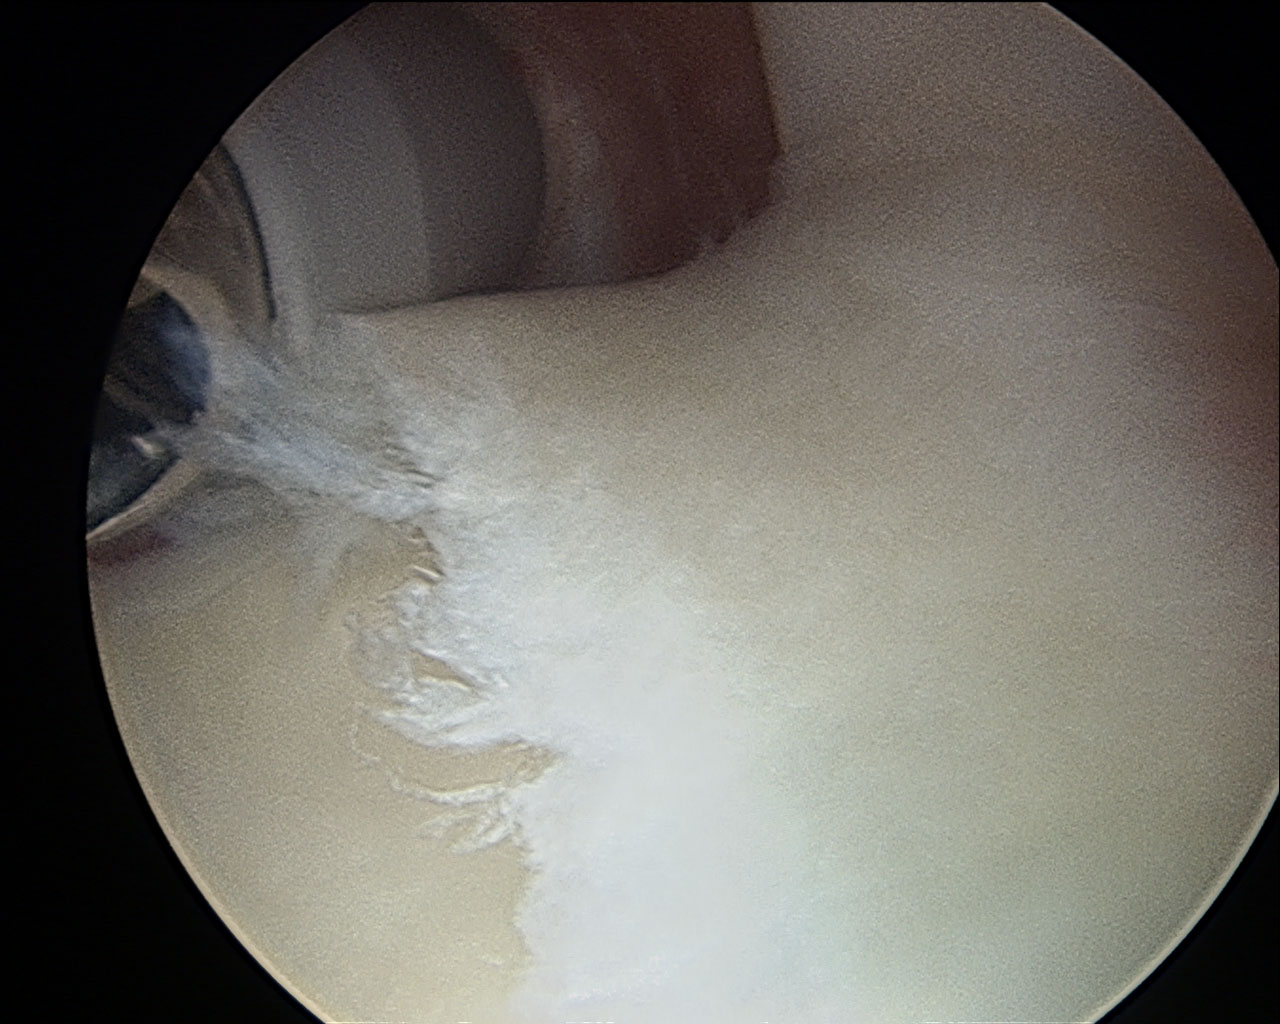

tibial plateau after being cleaned up…aka removing rough flaking articular cartilage

seriously. The second doctor strongly suggested we scope the knee; I agreed this was a good idea so that we could actually see WTF was going on (my surgery actually got moved up because floating cartilage got wedged and I couldn’t straighten or put weight on the leg). In surgery it turned out that the spot on the knee had a pretty good amount of damage to the articular cartilage, but wasn’t actually a hole, I still had half the thickness of my articular cartilage. This was good.  So they cleaned up the medial condyle, the tibial plateau, behind the knee cap (all had rough, fraying articular cartilage), and removed a couple floating pieces of cartilage.

• Shoulder: On April 28, 2012 I went from being very excited, to rather pissed very quickly. I hit a PR on a TGU with a barbell at 70kg on the right side.  I went to match on the left, and as I went to hip bridge, I began to lose the barbell backwards…instead of dumping as I should have, I instinctively pressed it out and at the top I felt a pop. This was not good. The next day I couldn’t really move the arm, and I started with acupuncture and treatment immediately, after having it checked out and they thought it was a rotator cuff tear of some sort. So I took it easy on the shoulder for May and June, it really didn’t hurt me that badly, but I want to be performing and feeling well so we got it checked out with a MRI and it showed a probable labrum tear in addition to me having something called an OS-acromiale. So, surgery was decided on because if I was already rehabbing my knee, lets get a

tool in my shoulder

slap 2

anterior labrum flap & some glenoid fossa issues

2 for one and also because I was PRing on surgical procedures. #PReveryday  Turned out I had a lot of stuff going on in there: shaved the end of the “loose” acromiale, fixed a minor slap 2 tear, fixed a minor biceps tendon tear, sucked out some bursitis, cleaned up a large tear in the anterior labrum, and also cleaned up some fraying articular cartilage in the glenoid fossa. Yeah, lots of suck.  **second take home. stick to your training plan. especially the proper warm up. I did neither on both injuries and that isn’t gonna happen again.**